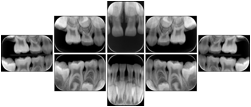

Intra-oral radiography typically involves acquisition of multiple images of various parts of the dentition. Many digital radiographic systems offer customized templates that are used for displaying the images in a study on the screen. These templates may also be referred to as mounts or view sets. The Structured Display Object represents a standard method of encoding and exchanging the layout and intended display of Structured Displays. A structured display object created in this manner could be stored with a study and exchanged with images to allow for complete reproduction of the original exam.

1. A patient visits a General Dentist where a Full Mouth Series Exam with 18 images is acquired. The dentist observes severe bone loss and refers the patient to a Periodontist. The 18 images from the Full Mouth Series along with a Structured Display are copied to a DICOM Interchange CD and sent with the patient to see the specialist. The Periodontist uses the CD to open the exam in his Dental Radiographic Software and consults via phone with the General Dentist. Both are able to observe the same exam showing the images on each user's display using the exact same layout.

Intra-oral Full Mouth Series Structured Display

Figure OO-1. Intra-oral Full Mouth Series Structured Display